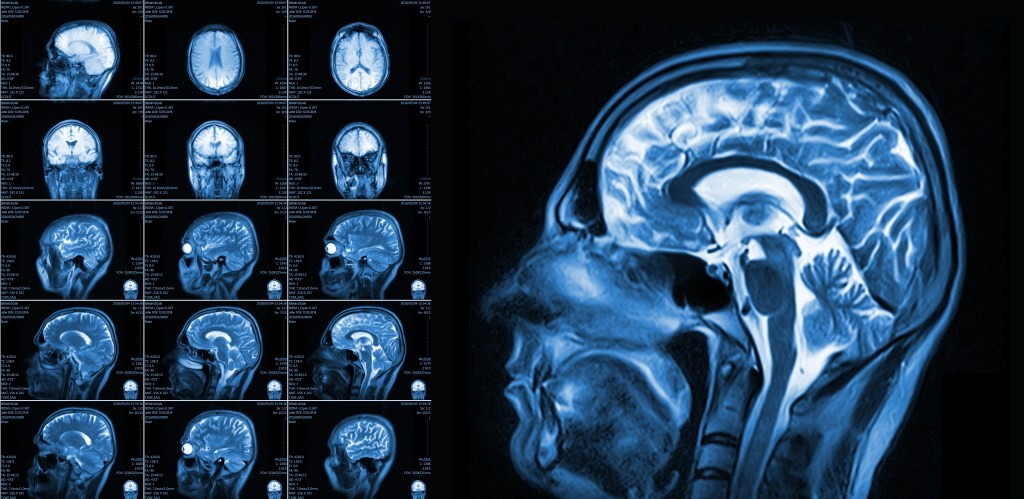

Na koniec badań zaobserwowano wyraźne korzyści w zakresie przepływu krwi w mózgu. Obrazowanie wykazało znaczną poprawę w zakresie przepływu krwi do mózgu. Po 16 tygodniach spożywania orzechów przepływ krwi do mózgu ogólnie wzrósł o 3,6% w porównaniu z okresem kontrolnym. „CBF is an important physiological marker of brain vascular function and refers to the amount of blood that flows through the brain, delivering oxygen and nutrients that are essential for maintaining brain health,” powiedział w oświadczeniu dr Peter Joris, autor badania. Niskie CBF związane jest ze spadkiem funkcji poznawczych i może wpływać na takie funkcje jak uwaga, szybkość psychomotoryczna i pamięć. Gdy Joris i jego współpracownicy przeanalizowali istotę szarą mózgu, stwierdzili, że przepływ krwi wzrósł o 4,5%. Płatów czołowych zyskały 6,6%, a płatów skroniowych 4,9%. Te regiony odgrywają kluczową rolę w pamięci, języku, podejmowaniu decyzji i kontroli emocji. Te korzyści naczyniowe przekładają się na lepsze przypominanie. Podczas testu pamięci osoby, które jadły orzechy, rozpoznawały więcej słów z listy, którą widziały 20 minut wcześniej, w porównaniu z okresem kontrolnym. „Po raz pierwszy udowodniliśmy, że spożycie orzechów poprawia funkcję naczyniową mózgu u zdrowych starszych dorosłych,” dodał Joris.